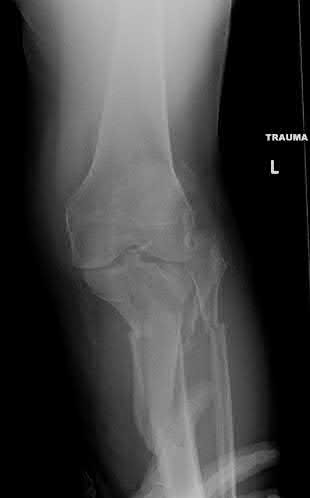

Question 20

A 3-year-old girl is evaluated for severe, progressive bilateral genu varum. Radiographs demonstrate medial metaphyseal beaking, fragmentation, and depression of the proximal medial tibial physis.

According to the Langenskiöld classification of infantile Blount's disease, at which stage does an overt physeal bony bar (epiphyseal-metaphyseal bridge) definitively form across the medial physis, conferring a high risk of recurrence without bar excision?

Explanation

The Langenskiöld classification describes progressive radiographic changes in infantile Blount disease. Stage I-IV show worsening metaphyseal beaking and stepping. Stage V shows a deep cleft separating the medial epiphysis into two portions. Stage VI is definitively characterized by the formation of a solid medial physeal bridge (bony bar) between the epiphysis and metaphysis, halting medial growth completely and often requiring bar resection along with osteotomy.